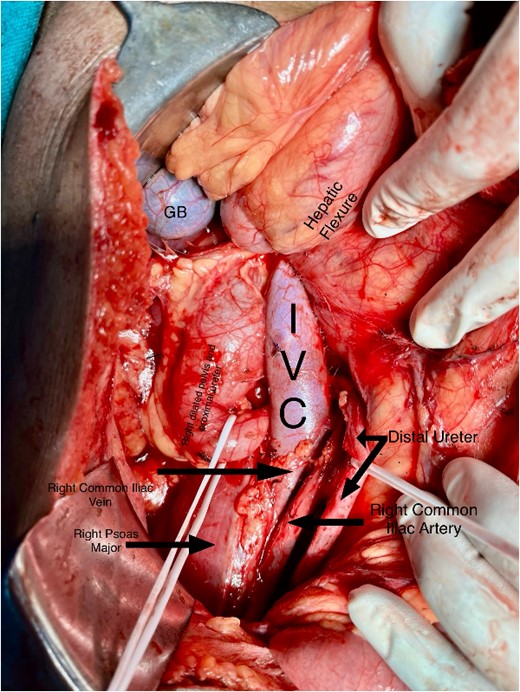

A midline incision was given, and the abdomen was opened from 4 cm below the xiphisternum to 3 cm above the pubic symphysis. The ascending colon along with the hepatic flexure was completely mobilized medially to expose the retroperitoneum. Careful dissection was done to identify the IVC and its the relations to the right ureter. The proximal dilated ureter and right pelvicalyceal system were identified, and dissection was continued laterally. The ureter was traced and noticed to course behind the IVC at the level of the L2–L3 vertebra, exiting to lie medially in the groove between the IVC and the aorta (Fig. 3). The ureter was divided proximal to the point where it coursed behind the IVC until it came out medial to IVC (Fig. 4). The retrocaval segment was brought anteriorly, resected from the normal distal ureter, and ureteropelvic anastomosis was done using 3–0 Polyglactin sutures lateral to the IVC (Fig. 5). This procedure eliminated the compression on the ureter. An abdominal drain was placed.

Intraoperative image showing the course of the retrocaval ureter and the important structures around it.